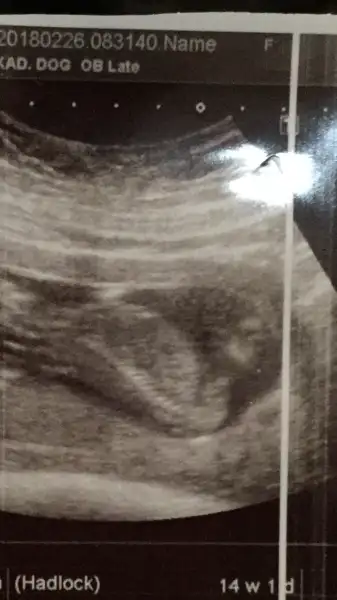

Kızlar kuzenim gittiğim hastaneye güvenmediğini dile getirdi kafam karıştı doktor erkek dedi penisi dedi gösterdi harta usg si de bu yanılma olurmu ben yinede ilk oğlumdaki gbii detaylıya kadar beklerim ama gittiğimde devlet hastanesi gibi bi hastane bilemedim doktora hiç sormadan ben kendi söyledi hatta kız bekliyordum diye defalarca emin misiniz dedim bak penisi burda dedi

Eklentiler

• B799A313-E3CC-427D-A00E-2C1D174ACE15.webp

B799A313-E3CC-427D-A00E-2C1D174ACE15.webp

11,6 KB · Görüntüleme: 172